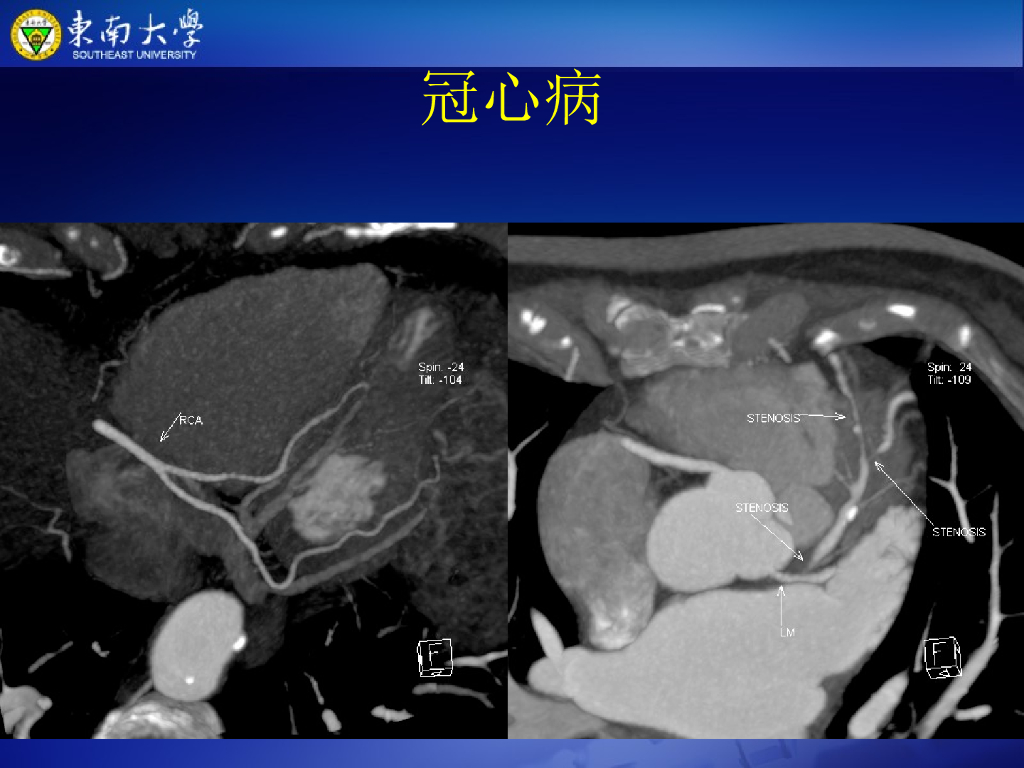

《放射诊断学》演示文稿-高心、肺心、冠心病--实习.pdf